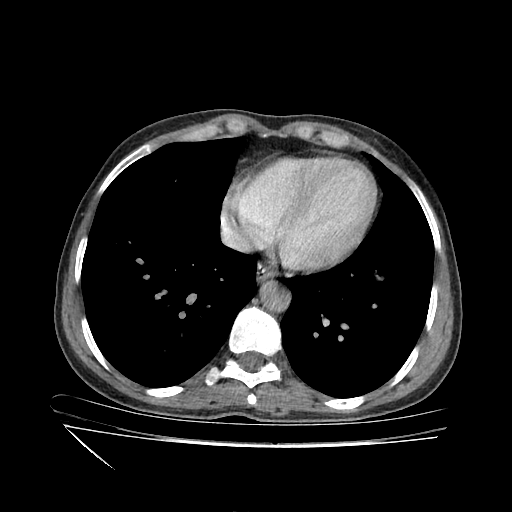

Original VENOUS CT scan

Full window (WL 1023.5, WW 4095 β†’ Low βˆ’1024, High +3071)

Actual HU range: [-1024.0, 1080.0]